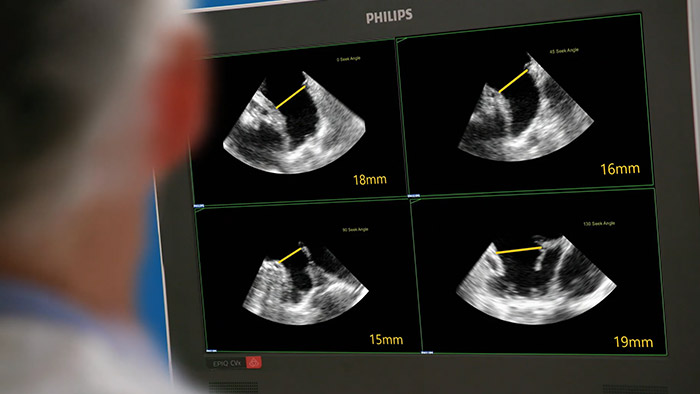

Avaliação do apêndice atrial esquerdo de forma rápida, fácil e intuitiva. A solução de AAE da Philips no EPIQ CVxi.